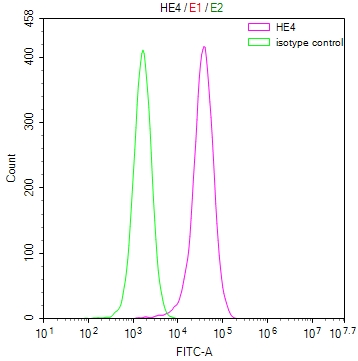

The image on the left is immunohistochemistry of paraffin-embedded Human brain tissue using CSB-PA196653(ABI1 Antibody) at dilution 1/40, on the right is treated with synthetic peptide. (Original magnification: ×200)